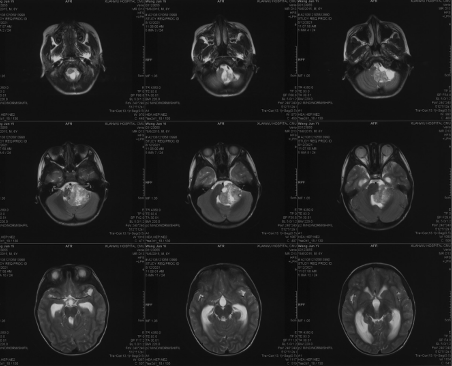

Preoperative imaging MRI-T2

Preoperative imaging MRI-T1

Preoperative MRI-DWI